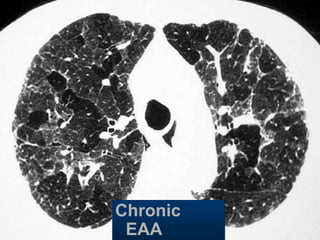

Chronic

EAA

Hypersensitivity pneumonitis

Extr. Allerg. Alveolitis (EAA)HRCT

Morphology

chronic: fibrosis

Intra- / interlobular septal thickening

Irregular interfaces

Traction bronchiectasis

acute - subacute

acinar (centrilobular) unsharp densities

ground glass (patchy - diffuse)